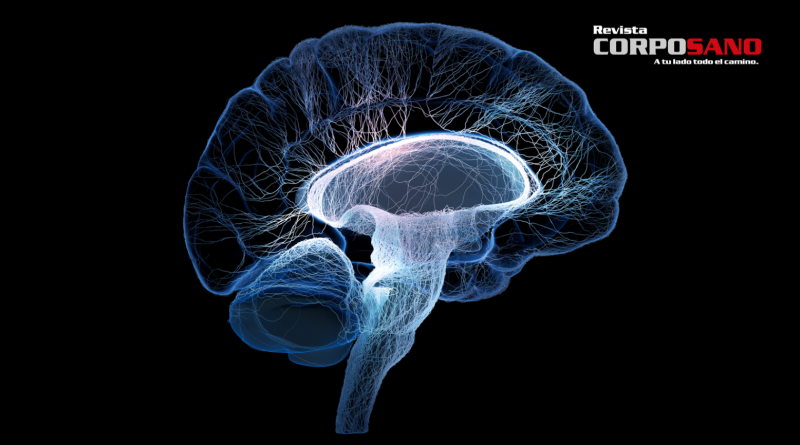

El cerebro es el órgano más complejo de nuestro cuerpo y el único que reconoce su propia existencia. Aquí están algunos datos que no sabías sobre él:

Hay más de 50 mil millones de neuronas en tu cerebro. y más de 500 kilómetros de vasos sanguíneos.

Hay más de 500 kilómetros de vasos sanguíneos en tu cerebro.